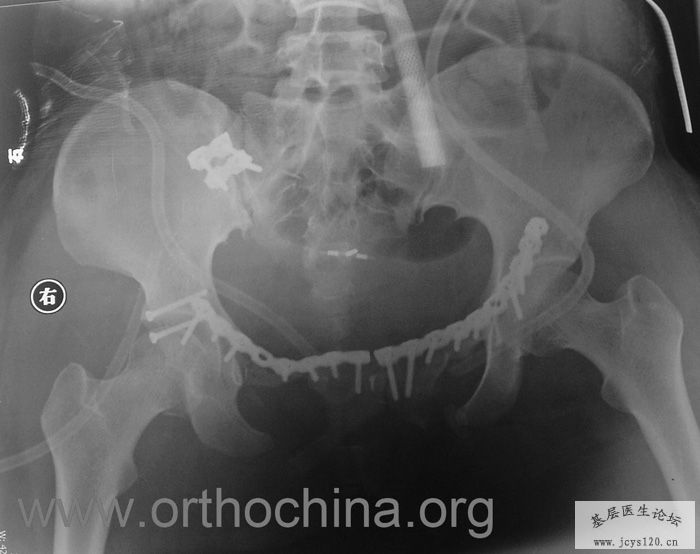

患者,女,28岁,车祸中骨盆轧伤后疼痛功能障碍1小时。查体:休克外貌,烦躁不安。头颈胸腹无异常,脊柱无异常,两下肢血供及感觉正常。骨盆挤压分离试验阳性。阴道、尿道、直肠、腹内脏器无损伤。住院后抗休克、骨牵引及对症治疗1周后,行前后联合入路手术。股骨头骨折复位后用可吸收螺钉固定,骶髂关节、髋臼前后柱、对侧耻骨上下支用骨盆重建钛板固定,术中出血1200ML,手术时间8小时。部分图片如下: